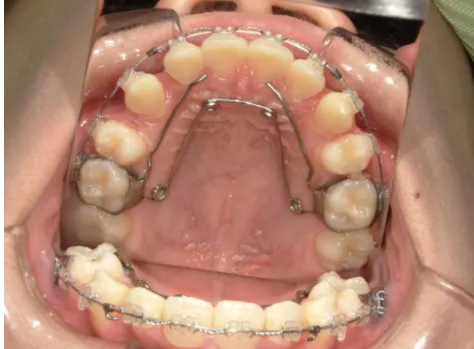

治療中⑧高1:15y11m 抜歯治療中

治療中⑨高2:17y1m 抜歯治療中

治療後⑩高2:17y7m 抜歯治療終了